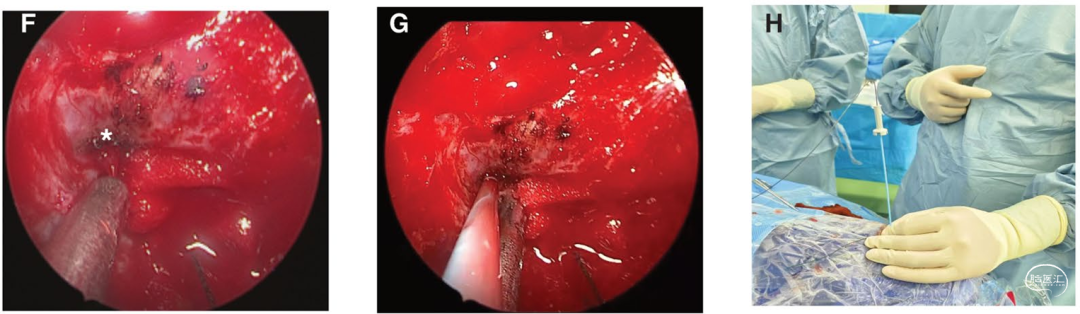

团队将经蝶入路与介入治疗结合,在神经内镜的全程直视下,直接穿刺海绵窦内侧壁的硬脑膜,从而绕开已闭塞的天然静脉,开辟出位于传统通路之外路径。这条路径的核心优势在于可视化,医生能够清晰辨认局部血管搏动,有效避开重要的神经与血管结构。

手术在复合手术室内完成。介入团队经股动脉穿刺,留置造影导管用于术中实时评估;神经外科团队则经鼻腔入路,在内镜下显露并切开海绵窦内侧壁硬膜。随后,在双重视觉引导下,将工作鞘管精准置入海绵窦腔内,建立起直达瘘口的稳定通道。

栓塞采用了分阶段栓塞的策略:首先置入弹簧圈以减缓血流,随后注入onyx-18液体栓塞剂,完整填充瘘腔及引流静脉,形成致密铸型,最终实现异常血流的永久阻断。